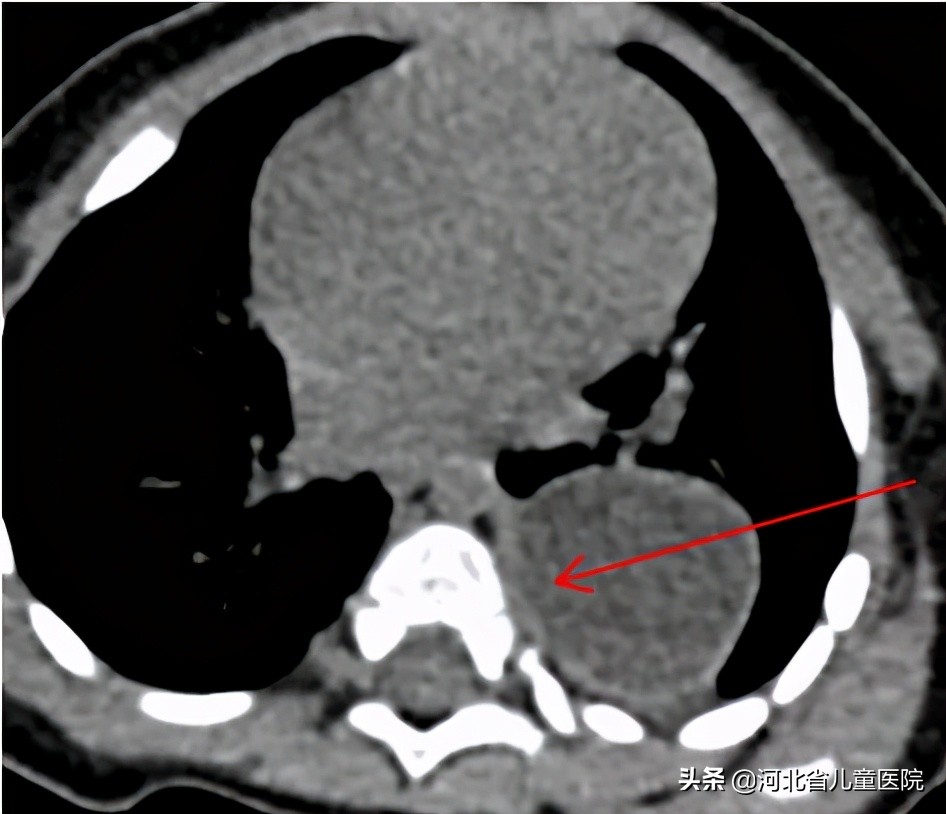

巨大纵隔占位

9月大的孩子

9个月的乐乐,因为咳嗽检查胸部CT,发现存在巨大的纵隔占位,乐乐爸妈很是费解,孩子平时也没啥症状,怎么会纵隔长个东西呢?

所幸,乐乐的纵隔占位经手术切除,术后恢复顺利,病理回报是良性的囊肿,大家悬着的心也终于能放下了。